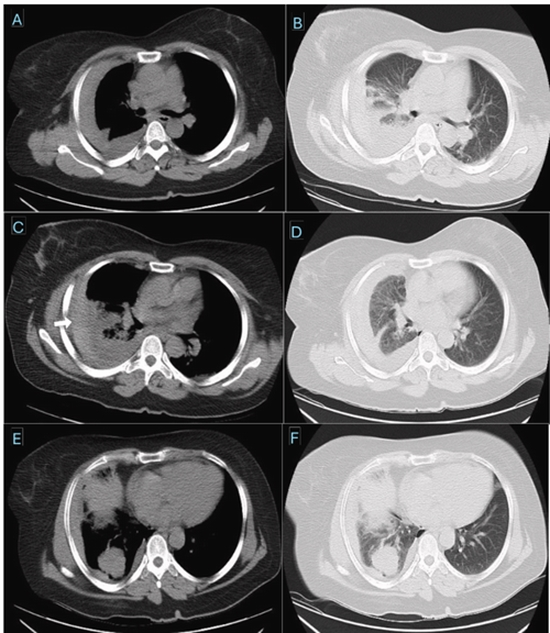

CT-guided transthoracic lung biopsy is an essential diagnostic technique for evaluating pulmonary lesions. Although rare, major complications such as hemothorax can be life-threatening. We report the case of a 35-year-old woman who developed a rapidly enlarging right hemothorax several hours after CT-guided core needle biopsy of a pleura-abutting right lower lobe mass. There was no arterial extravasation, and chest tube drainage yielded approximately 1500 mL of dark, clotted blood, suggesting a venous or tumoral source. The patient remained hemodynamically stable and achieved complete recovery with conservative management. This case highlights that even massive post-biopsy hemothorax can be successfully treated non-operatively in stable patients by adhering to trauma-based management principles.